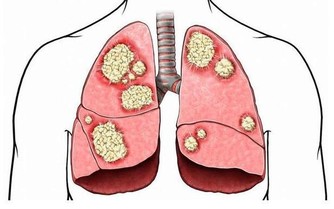

這句話講的是什麼意思呢?頸七椎向下相連的是胸椎的一椎、二椎,這兩個椎體與肺相通,是通往肺的通路,當頸椎扭傷一定牽連到胸椎的一、二椎;腰椎向上相連的是胸十椎、十一椎、十二椎,十一椎、十二椎與脾、胃相通,是通往脾胃的通路,當腰椎扭傷一定牽連到胸十、十一椎。

胸椎的每個椎體,均與臟腑相通,是通往臟腑並為臟腑提供氣血的通路,當胸椎第一、二椎體發生了錯位,必然造成通往頸椎,肩膀的經脈運行受阻,氣血循環不暢,影響對頸椎和胳膊等部位的供血,導致通往頭部和肩部經絡受阻,血液循環不暢通,因而在頭部出現疼痛和胳膊發麻的病症。當錯位的胸椎經復位治療,一旦復位“開閘放水”,經脈通暢,活血化瘀,就迅速的滿足了頭部和胳膊缺血的需要,使頭痛和手指發麻的病症及時得到恢復。

胸一椎:上臂手腕指,食管氣管小魚際;心悸胸痛伴咳喘,肩臂疼痛難呼吸。

胸二椎:循腋至肘上;三至十二胸肋肌;咳嗽氣喘上臂痛,心悸心慌心胸疾。